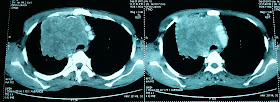

A chronic smoker is admitted with us, his complaints are right sided chest pain and facial pufiness noticed every day when he wakes up in the morning.

Here is the CT thorax.

Pancoast tumor ...